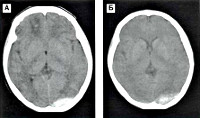

Субдуральные гематиомы чаще возникают при стремительных родах, когда имеет место резкое смещение костей черепа. Наиболее часто травмируются сосуды, впадающие в верхний сагиттальный и поперечный синусы и сосуды намета мозжечка. Субдуральные гематомы могут быть одно- или двусторонними. Непосредственно после рождения неврологические нарушения выражены не резко, и это состояние обычно диагностируют как нарушение мозгового кровообращения I-II степени. Состояние ребенка постепенно ухудшается. Образовавшаяся гематома вызывает сдавление жизненно важных центров мозга, вызывает дислокацию ликворных путей. Кожные покровы бледные, холодные, дыхание учащенное, нерегулярное, пульс аритмичный. Мышечный тонус снижен. Безусловные рефлексы отсутствуют или угнетены. Корнеальный и конъюнктивальный рефлексы отсутствуют. Ребенок не сосет, не глотает. Постепенно нарастают симптомы внутричерепной гипертензии, набухают роднички, может возникнуть расхождение черепных швов. Могут быть очаговые или генерализованные клонико-тонические судорожные приступы. При нераспознанной гематоме через 7-10 дней происходит ее инкапсуляция с последующей атрофией мозговой ткани. Лечение нейрохирургическое. Субтенториальные субдуральные кровоизлияния (кровоизлияния в заднюю черепную ямку) характеризуются особой тяжестью. С момента рождения нарастают симптомы сдавления ствола мозга: ригидность затылочных мышц, анизокория, стойкое отведение глаз в сторону, грубый нистагм, тонические судороги. Прогрессируют брадикардия, расстройство дыхания, вялость, гипо- и арефлексия, расстройство сосания и глотания.

Диагностика родовых кровоизличяний основывается на тщательном изучении акушерского анамнеза, течения родов, детальном неврологическом обследовании и применении специальных методов исследования УЗИ, КТ, МРТ головного мозга